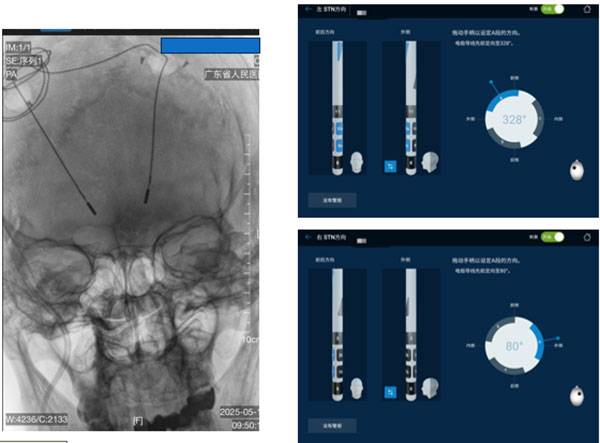

“简单来说,有三大武器,令DBS放得准、打得准、自调控。”聂坤介绍,首先,目前的机器人辅助植入,已实现亚毫米级精准定位,放得准;第二,方向性电极,可以从传统的全向刺激到定向调控,精准对焦目标核团,并且实现个体化的远程调控,打得准;而搭载了脑机接口和人工智能的闭环智能脑起搏器,则可以实时感知分析,进行自适应调节。

机器人辅助植入DBS,实现亚毫米级精准定位

“现在的闭环智能脑起搏器,就像一位24小时智能健康管家。它能够读懂患者大脑的脑电信号,通过‘读脑-分析-反馈-调节’,动态自适应调整参数,根据每位患者的症状给到个体化精准治疗。”聂坤介绍,这三项技术可叠加应用,标志着脑起搏器治疗已从“经验依赖、固定参数”的传统模式,迈入“精准植入、定向调控、智能闭环”的新时代。

方向性电极,定向调控打得更准